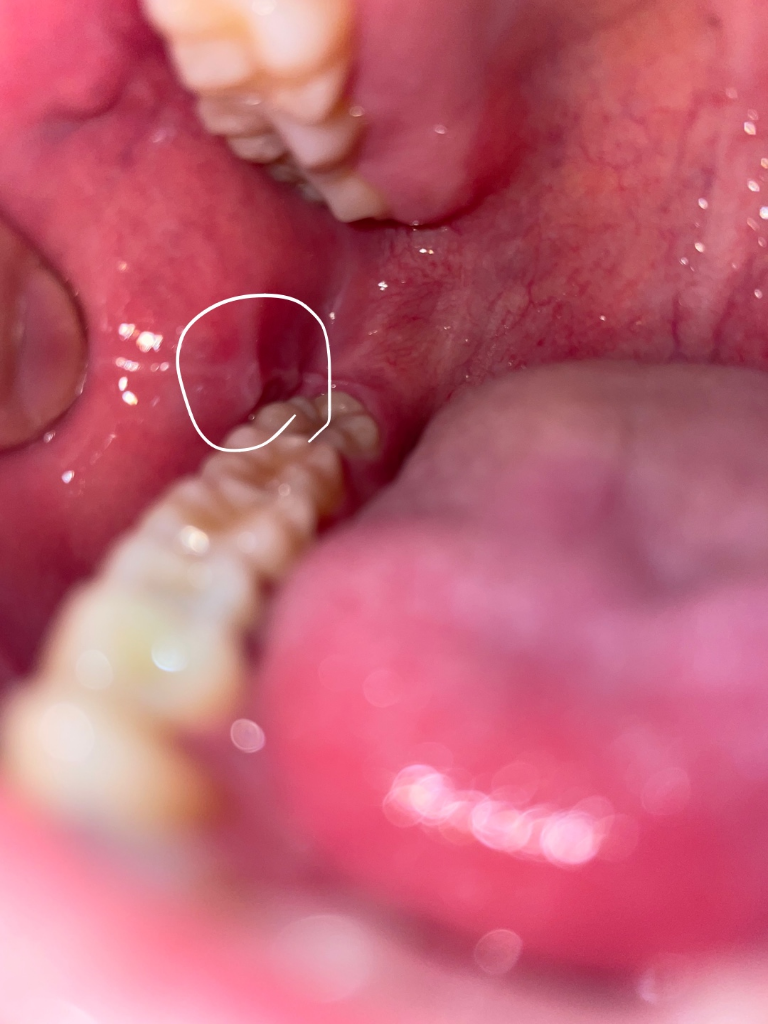

양쪽 어금니 쪽 볼에 혹?처럼 뭐가 생겼어요 깨문기억은 없는데 혹시 구강암이런것과 관련있나요?

한 3일전쯤까진 없었는데 그쯤 양쪽 어금니 쪽에 볼에 혹? 염증? 같은 그런게 생겼어요

그리고 사진에 보면 어금니 뒤쪽 흰색부분이 있는데 이건 왜 그럴까요 이건 언제부터 생긴건지는 모르겠습니다. 잘 안보이실까 하여 표시안한 원본사진도 첨부합니다

해당부위는 볼의 연조직이 치아 사이에 밀려 들어가면서 생기는 증상으로 보입니다.

구강암이 아니고 볼이 치아에 씹혀서 생긴겁니다. 문제가 잇는건 아니니 너무 걱정하지마세요.

사진상으로는 씹어서 생긴 외상성 궤양이 맞습니다

특별히 치아에 보철치료나 충치치료를 하고 생긴 변화가 아니기 때문에 치과적으로 처치를 해줄 건 없고 외상성 궤양도 시간이 지나면 자연스럽게 회복됩니다. 좀 더 빠른 회복을 위해서는 구강 내에 적용하는 연고를 바르셔도 좋습니다.